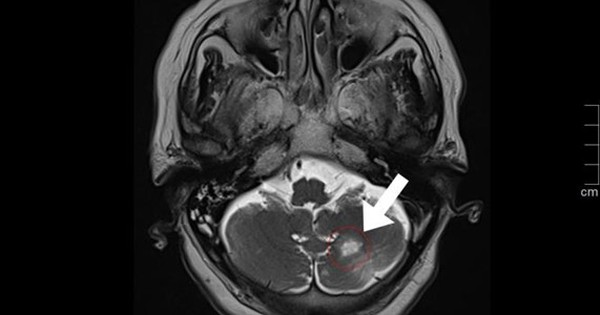

Bệnh nhân được chỉ định xét nghiệm huyết học, sinh hóa và chụp thêm MRI sọ não để loại trừ nguy cơ đột quỵ cấp. May mắn các chỉ số xét nghiệm không cho thấy tình trạng nhiễm trùng. MRI sọ não cho thấy bệnh nhân từng bị nhồi máu não bán cầu tiểu não trái. Hiện bệnh nhân tỉnh táo, khỏe, đi lại tốt.